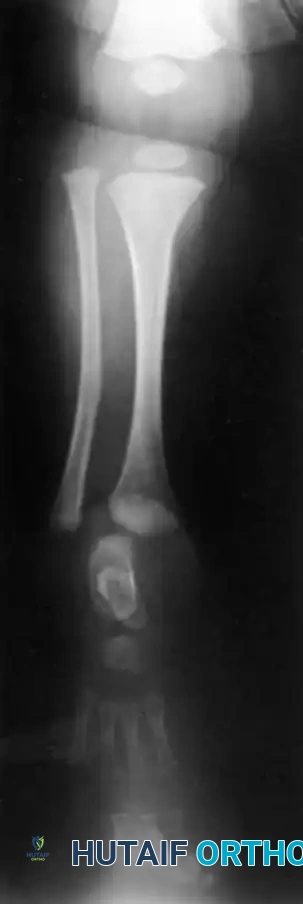

- Type 2 Deformity: A proximal tibia of varying size is present and ossified at birth. The fibula is usually normal in size, but the fibular head is proximally dislocated.

The treatment of choice is a proximal tibiofibular synostosis combined with a Syme amputation or complex distal reconstruction. Creating a synostosis between the fibula and the proximal tibia creates a uniform, in-line, weight-bearing mechanical axis. If the fibula is not surgically transferred and fused to the tibia, a peculiar, curved, hypertrophied fibula develops, causing a severe secondary deformity. Fusing the fibula underneath the tibia encourages its hypertrophy in a mechanically advantageous alignment.

By fusing the fibula to the tibia, the surgeon prevents the progressive lateral bowing and hypertrophy of the fibula that inevitably occurs if it is left in its native, eccentric position. This synostosis provides a robust, centralized bony column that can later be lengthened or fitted with a prosthesis following a distal Syme amputation.

For patients undergoing tibiofibular synostosis and distal amputation (Type 1B/2), the limb is protected in a cast until radiographic union of the synostosis is confirmed. Once healed, the patient is fitted with a specialized prosthesis that accommodates the reconstructed limb. Because these limbs often lack normal longitudinal growth, the patient will require frequent prosthetic adjustments and may eventually be a candidate for limb lengthening procedures (e.g., Ilizarov or Taylor Spatial Frame) as they approach skeletal maturity.